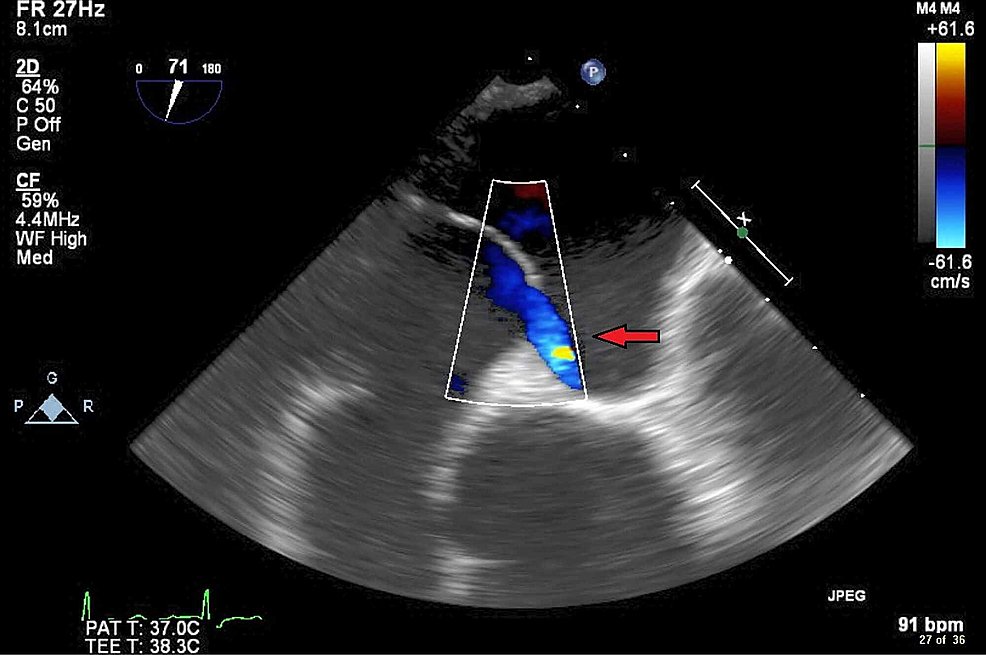

Note - this is not technically an ASD (atrial septal defect) - because the septa are all intact. In an ASD, part of the septum is missing or perforated. Note in this image, and our clip, the flow sneaks underneath the curtain, through the unsealed, patent, foramen ovale! (8/8)